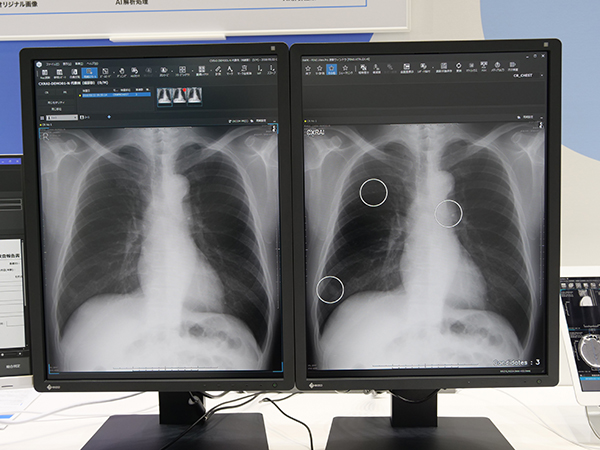

ブース内では,AI解析ソフトウエア“CXR Finding-i”でデモンストレーションも実施した。胸部X線画像から肺結節や浸潤影の候補などをマーキングして提示する。

肺結節・浸潤影の候補を提示する“CXR Finding-i”